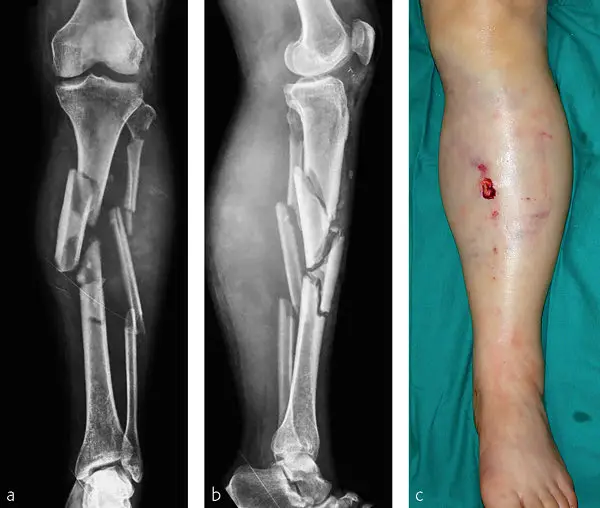

Sharing pictures of a similar injury, noting that 'it's not hers', he continued: "This is called an external fixator (‘x-fix’) and is being used to help stabilise the fractured tibia (and maybe more)."